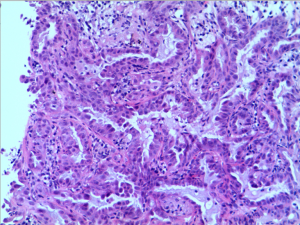

A 47-year-old, non-smoking female was referred to our hospital in January 2018 with a 1-month history of cough and phlegm. A chest computed tomography (CT) scan revealed a 5.0 cm mass in the left lower lung associated with multiple nodules in both lungs (Figure 1). Tumor biopsy pathology conducted on January 31, 2016, revealed that the patient had a stage IV (cT4N3M1) adenocarcinoma. Hematoxylin and eosin (H&E) staining revealed a typical morphology for adenocarcinoma cells (Figure 2).

Thoracic radiotherapy followed by three cycles of chemotherapy with pemetrexed (750 mg) and cisplatin (40 mg) were administered between February 2018 and May 2018. However, emission computed tomography (ECT) revealed tumor progression after one month and gemcitabine (1.5 g) and nedaplatin (120 mg) were prescribed. Unfortunately, the patient relapsed in August 2018 and a tumor progression was observed. An next-generation sequencing (NGS) analysis of the hydrothorax revealed a variant of EML4-ALK fusion (the allele frequency: 16.6%) (Figure 3) accompanied by a point mutation of KRAS (p.G13D, the allele frequency: 15.7%) (Figure 4). Based on molecular findings, treatment was initiated with crizotinib in September, 2018. After 2 months of therapy, the patient achieved a partial response (Figure 5). Afterwards, the patient was further administrated with crizotinib for 6.0 months with a stable disease before tumor progression. Written informed consent was obtained from the patient for publication of this case report and any accompanying images.